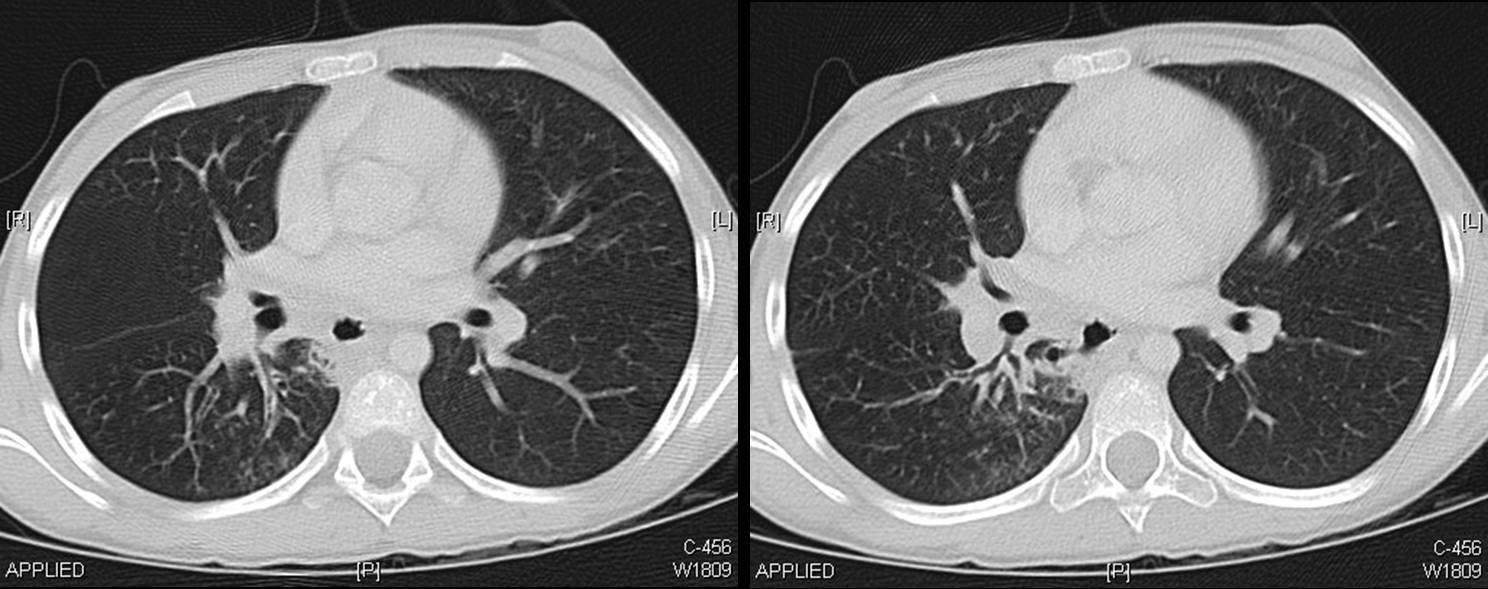

A CT scan of chest was done.

The following screen shows the images from the Chest CT.

| Figure 4-a | Figure 4-b | Figure 4-c |

| Figure 4-d | Figure 4-e | Figure 4-f |

| Figure 4-g |